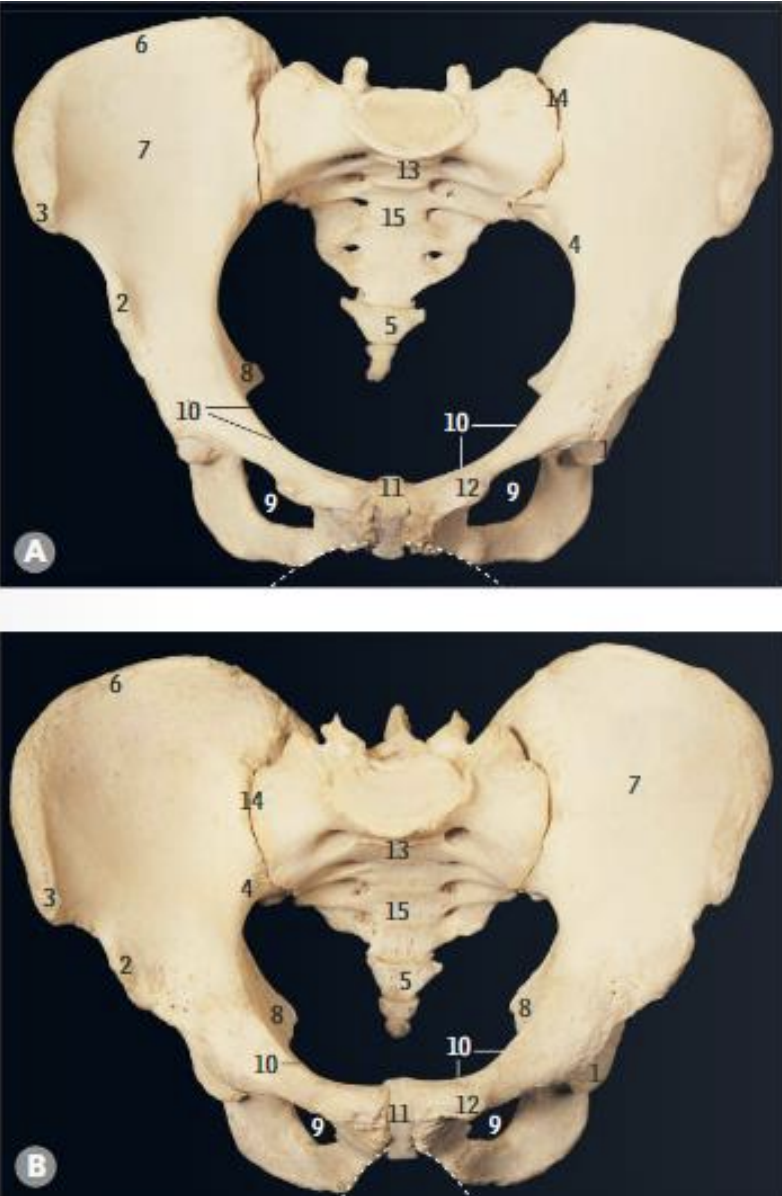

<p>What is structure 1?</p>

What is structure 1?

Sacrospinous ligament

<p>What is structure 2?</p>

What is structure 2?

Sacrotuberous ligament

<p>What is structure 3?</p>

What is structure 3?

Greater sciatic foramen

<p>What is structure 4?</p>

What is structure 4?

Lesser sciatic foramen